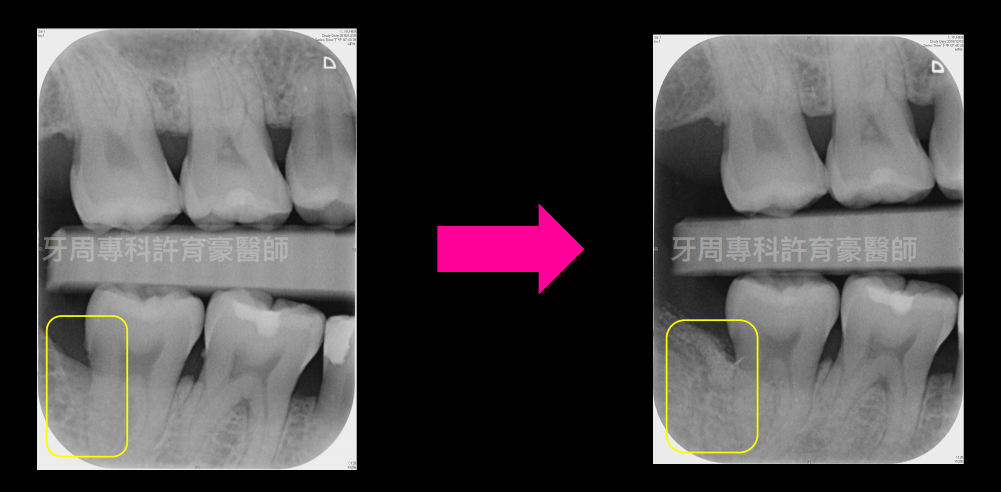

經牙周翻瓣再⽣⼿術後追蹤⼀年,原骨缺損處有明顯X光骨充填